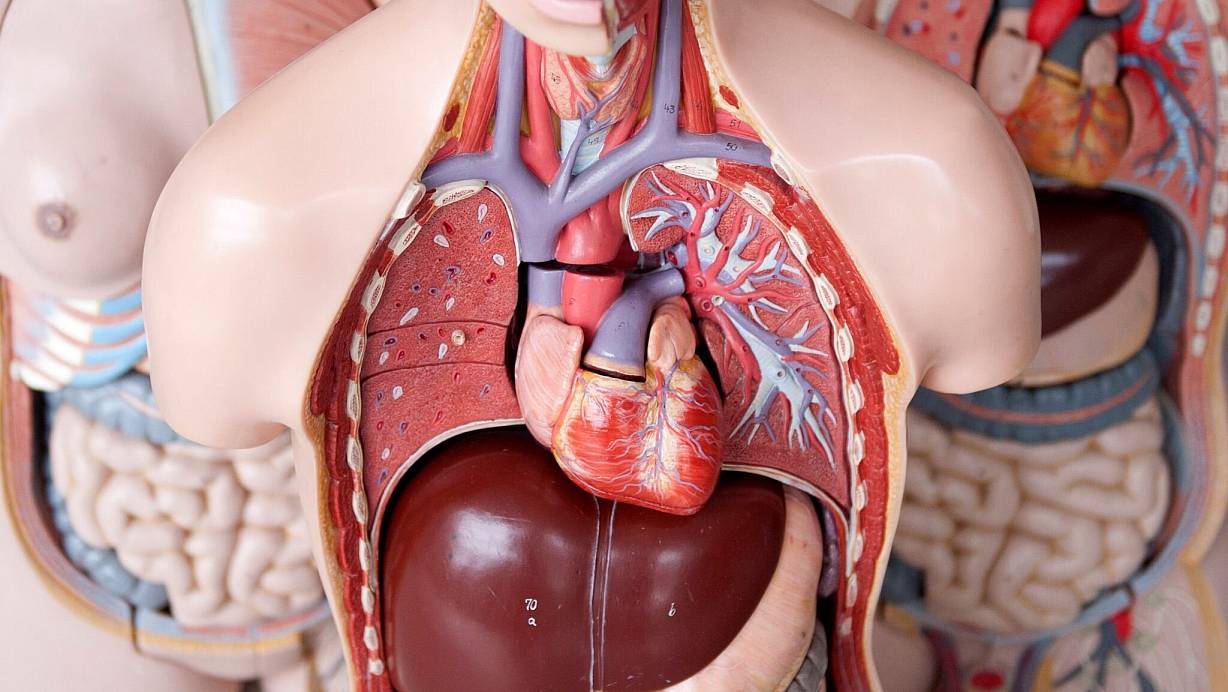

Zunächst: Was passiert bei einem Herzinfarkt eigentlich genau? Man spricht von einem Herzinfarkt, wenn Gefäße, die das Herz selbst mit Sauerstoff und Nährstoffen versorgen - sogenannte Koronararterien -, verschließen. Dazu kommt es, weil sich unter anderem Kalk in ihnen ablagert.